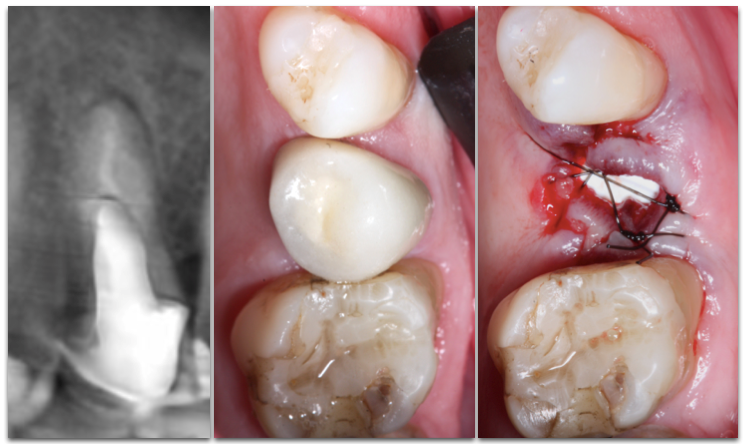

Paciente L.M., 53 anos, apresentava sensibilidade durante a mastigação e relatava mau hálito na região do dente 25. Durante análise clínica, a paciente apresentava sorriso alto (Figura 1). Após análise tomográfica, foi constatada uma perfuração radicular no dente em questão e que a raiz estava em contato com a tábua vestibular, sendo que esta possuía ≥1mm de espessura em seu terço cervical (Figura 2). Após a paciente concordar com o plano de tratamento, foi realizado a instalação imediata de um implante Cone Morse de corpo cônico (Due Cone 3.5×11, Implacil De Bortoli, São Paulo, Brasil), regeneração óssea guiada com osso bovino inorgânico e colocação de uma barreira regenerativa de politetrafluoretileno denso.

A utilização de um substituto ósseo de lenta taxa de substituição tem como objetivo compensar a reabsorção fisiológica ocorrida após a remoção de um dente condenado. Lembrando que a reabsorção apresenta índices mais elevados quando a tábua vestibular possui <1mm de espessura (biotipo fino) (Chappuis et al. 2015). No caso em questão, a paciente apresentava biotipo ósseo (≥1mm) e gengival espesso. Já com relação ao uso da membrana, a utilização desta evita a necessidade de procedimentos mais longos com objetivo de aproximar os bordos da ferida cirúrgica para proteger o alvéolo, além de reduzir significativamente o tempo do procedimento.